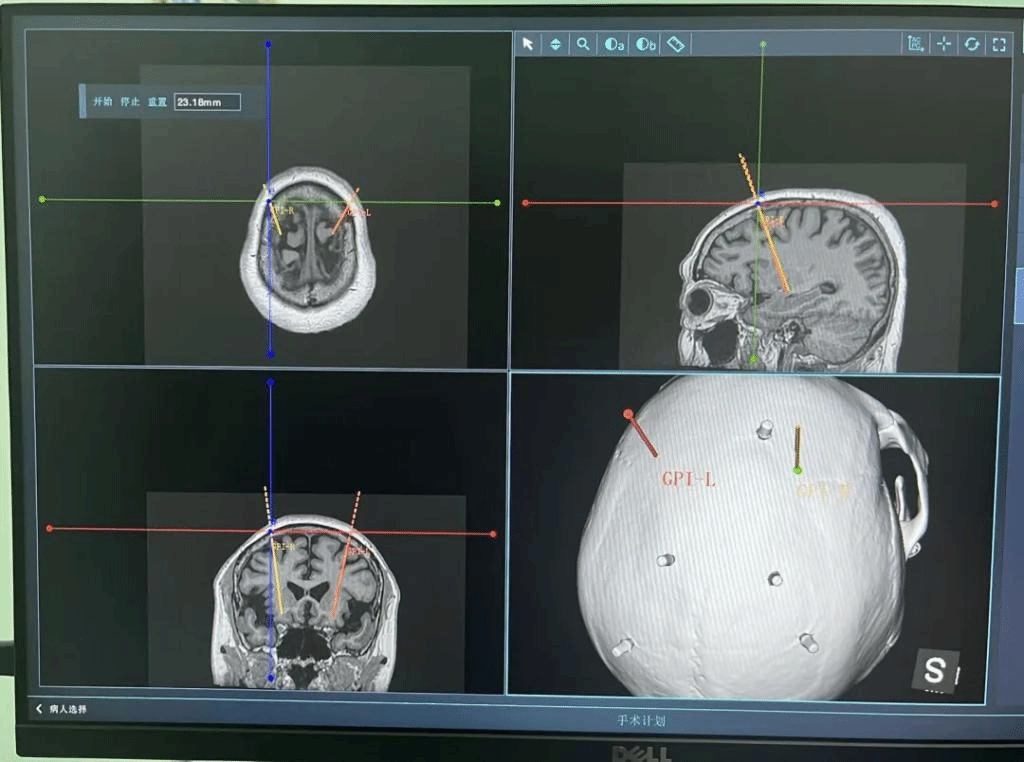

住院后,治疗团队为李阿姨完善了相关检查并制定了详细的手术方案。为了更精准地将刺激电极植入核团,团队决定采用先进的手术机器人来辅助植入定位。手术当日,团队使用手术机器人的导航系统将CT与术前完善的MRI进行图像融合,核团定位,植入路径的设置,并且在术中使用电生理监测,找到最典型的核团电信号。最终团队在手术机器人辅助下结合电生理监测工具,将电极精准植入到核团。

相比于传统DBS手术需要人工打头架、多次手动调整坐标和人为误差等缺点,手术机器人将可大大降低人为误差,电极植入更精准,术后神经调控效果更佳。